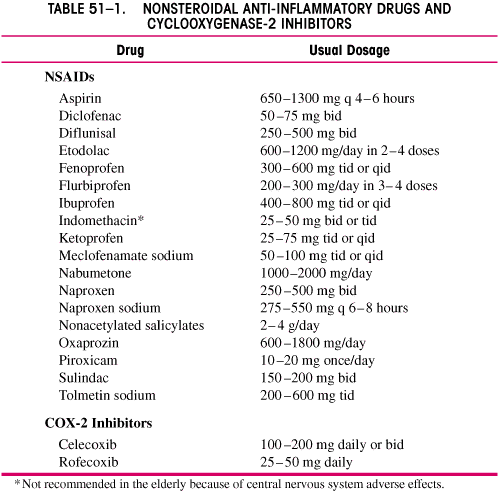

ARTRITA REUMATOIDA

ARTRITA REUMATOIDA Definitie. Artrita reumatoida este o boala sistemica cronica. Ea se caracterizeaza prin inflamatie infiltrativ-proliferativa a sinovialei articulare. PrevalentaCiteste tot ... 1560 cuvinte

Dimensiune medie

+ cu poze |